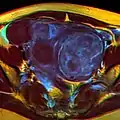

A very large (9 cm) fibroid of the uterus which is causing pelvic congestion syndrome as seen on CT

MRI image with multiple uterine leiomyomas